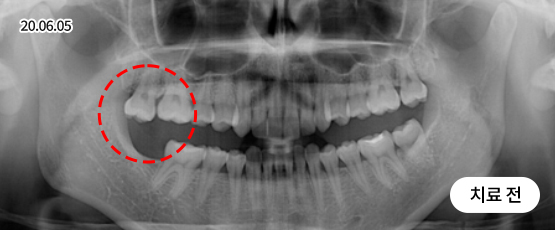

전악 임플란트

치아가 하나도 남아있지 않거나 전체적으로 상실된 경우 추천합니다.

치아의 기능을 다시 회복하기 위해 선택하는 임플란트입니다.

상실한 치아를 오랫동안 방치한 경우 상, 하악 잇몸뼈의 양도 부족한 경우가 많기 때문에 개개인의 건강 상태를 고려하여 정확한 수술 계획을 세워야 합니다.

• 치주질환으로 인해 음식을 씹기 힘들고,

미관도 좋지 않아 치아를 모두 발치한 후

전체 임플란트 수술을 하기로 결정

• 위 8개 + 아래 8개 임플란트 수술 진행 후

위 13개 + 아래 13개 (전체 치아)

임플란트 보철 제작 예정

• 임플란트 보철 완성